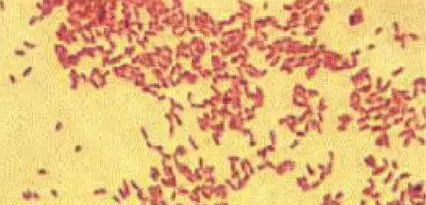

一,病原流行特点

布鲁氏杆菌在家畜中主要以牛羊猪最为常见,布氏杆菌分,牛型,羊型,猪型。而且三者都可传柒给人,其中,羊型布氏杆菌对人的致病性最强,危害最大。

布氏杆菌对热,各种,常用的各种消毒剂,紫外线都很敏感,但对低温干燥有很强的抵抗力,湿热60℃即可杀灭该菌,布氏杆菌对四环素类最敏感。